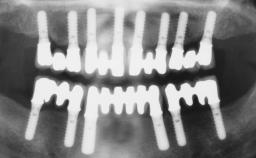

Jean-Pierre Bernard

Genève, Switzerland

- ITI Senior Fellow